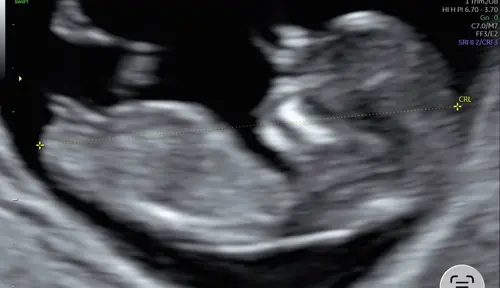

Misschien is de echo niet strak genoeg. Maar mijn gevoel zegt een meisje! Wat denken jullie?👀💕

Zie ik niet zo goed helaas